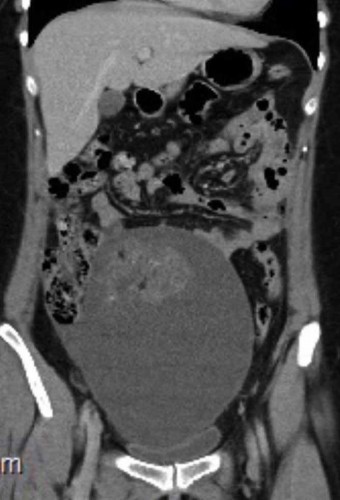

Doktorlara göre ultrason sonuçları iyi huylu bir kist olduğunu gösteriyordu. Fakat Louise’e yapılan biyopsi korkunç gerçeği ortaya çıkardı! Louise’in iki tane olgunlaşmamış teratomu vardı (Cenine özgü dokulardan oluşmuş bir tümör türü) Midesini kaplayan ve organlarına baskı yapan bu kötü huylu tümör böylece ortaya çıktı. Bu nadir kanser hücreleri genellikle 20’li yaşlardaki kadınlarda görülüyordu.

Doktorlar, Louise’in yumurtalıklarına ve fallop tüpüne de yerleşen tümörü temizlediler ve bu operasyon şans eseri doğurganlığına zarar vermedi.